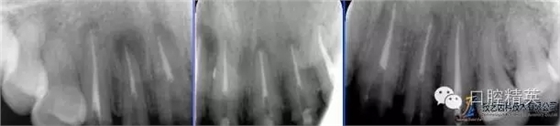

術前根尖片

術后根尖片